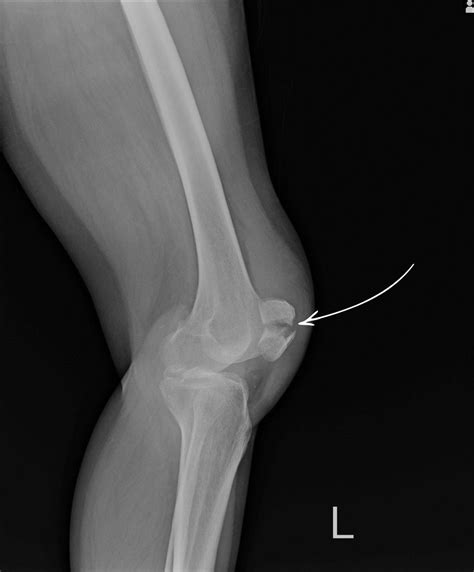

While only an X-ray or MRI can definitively diagnose a fracture, certain clinical signs are strongly associated with broken bones in the knee area. If you notice a combination of these, seek medical attention immediately.

When you arrive at the clinic or hospital, the medical team will likely perform a physical examination followed by diagnostic imaging. An X-ray is the gold standard for identifying fractures, but a CT scan may be required to assess the extent of the damage if the fracture extends into the joint space. Once the extent of the fractured knee symptoms is mapped, the doctor will determine whether non-surgical intervention—such as casting and bracing—or surgical fixation is required.